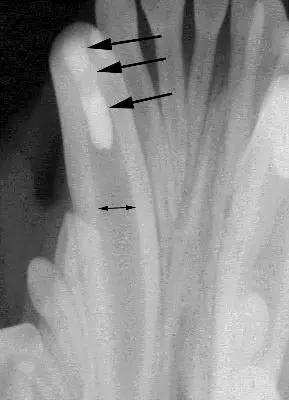

Seven years after initial treatment, the patient presented with an oblique complicated crown/root fracture of 404, which was of unknown etiology and duration. A complicated fracture is one that involves the root canal system of the tooth. The fracture extended under the gingival margin in an oblique fashion and the root canal could be clearly seen in the fracture site. Figure three shows the initial radiograph. Due to the geometry of the radiograph, the oblique nature of the fracture is not readily apparent.

The width of the root canals of both lower canine teeth are seen to much narrower when compared to the radiographs taken at the time of the initial treatment and fairly equal to one another, indicating that both of these teeth had remained vital (alive) and continued to mature. The apex of 404 is seen to be substantially shorter than the apex of 304 and 404 has a large periapical lucency. These finding would indicate that the fracture had been present for some time, leading to lytic changes and loss of apical root structure in 404 secondary to bacterial infection. Figure four shows an occlusal view of the fracture and Figure five shows a lateral view of the fracture. The oblique nature of the fracture can be appreciated. When the root canal system is exposed in a mature tooth, the best options for treatment are either root canal therapy or extraction of the tooth. The owner preferred to maintain as much function as possible and avoid the trauma of extracting a mandibular canine tooth.

Figure three, showing the apical lysis of 404 compared to 304. Tooth 304 has a small dark periapical lucency (arrow) that is actually the middle mental foramen, a normal anatomic structure usually located below the mesial root of the second premolar.